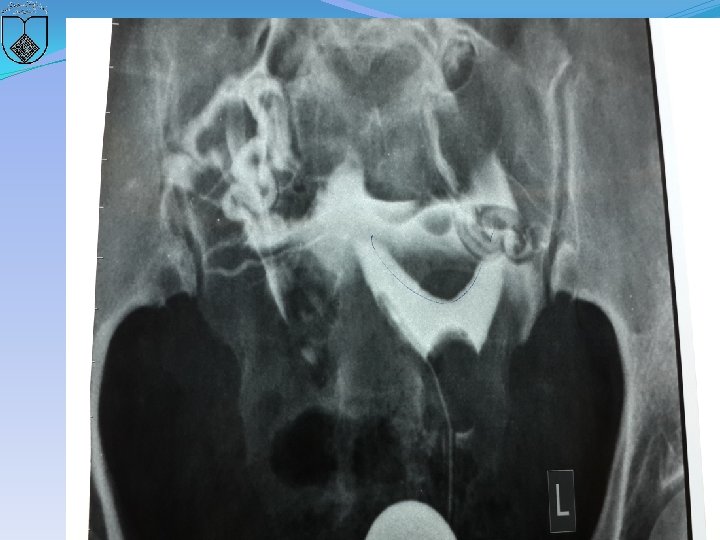

�ARE SEPTUM CHARACTERISTICS ASSOCIATED WITH WORSE REPRODUCTIVE OUTCOMES? �There is insufficient evidence to conclude that obstetric outcomes are different when comparing the size as defined by length or width of uterine septa. (Grade C) 65

66

67

68